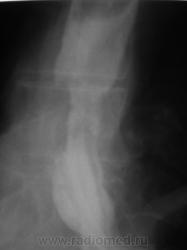

Пациент направлен на рентгенологическое исследование пищевода после ФГДС с диагнозом - "Пищевод Барретта".

Пациент первично был направлен в онкологический диспансер (областной). От туда он был направлен по месту жительства для производства ФГДС, которая и была проведена, был выставлен выше указанный диагноз.

После ФГДС, врач эндоскопист рекомендовал провести рентгеновское исследование пищевода.

Циркулярное сужение в н/3 + отсутствие складок на уровне поражения + формирующееся престенотическое расширение = рак н/3 пищевода. Ну, а Барреты? А Барреты потом...